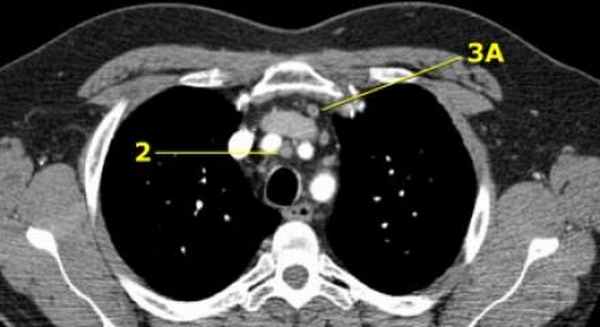

2R. Правые верхние паратрахеальные лимфатические узлы

Располагаются до левой стенки трахеи.

Верхняя граница: верхний край рукоятки грудины.

Нижний край: пересечение нижнего края плечеголовной вены с трахеей.

2L. Левые верхние паратрахеальные лимфатические узлы

Нижний край: верхний края дуги аорты.

На изображении слева представлены 2 лимфатических узла кпереди от трахеи, то есть 2R, так же виден небольшой преваскулярный лимфатический узел 3A группы.